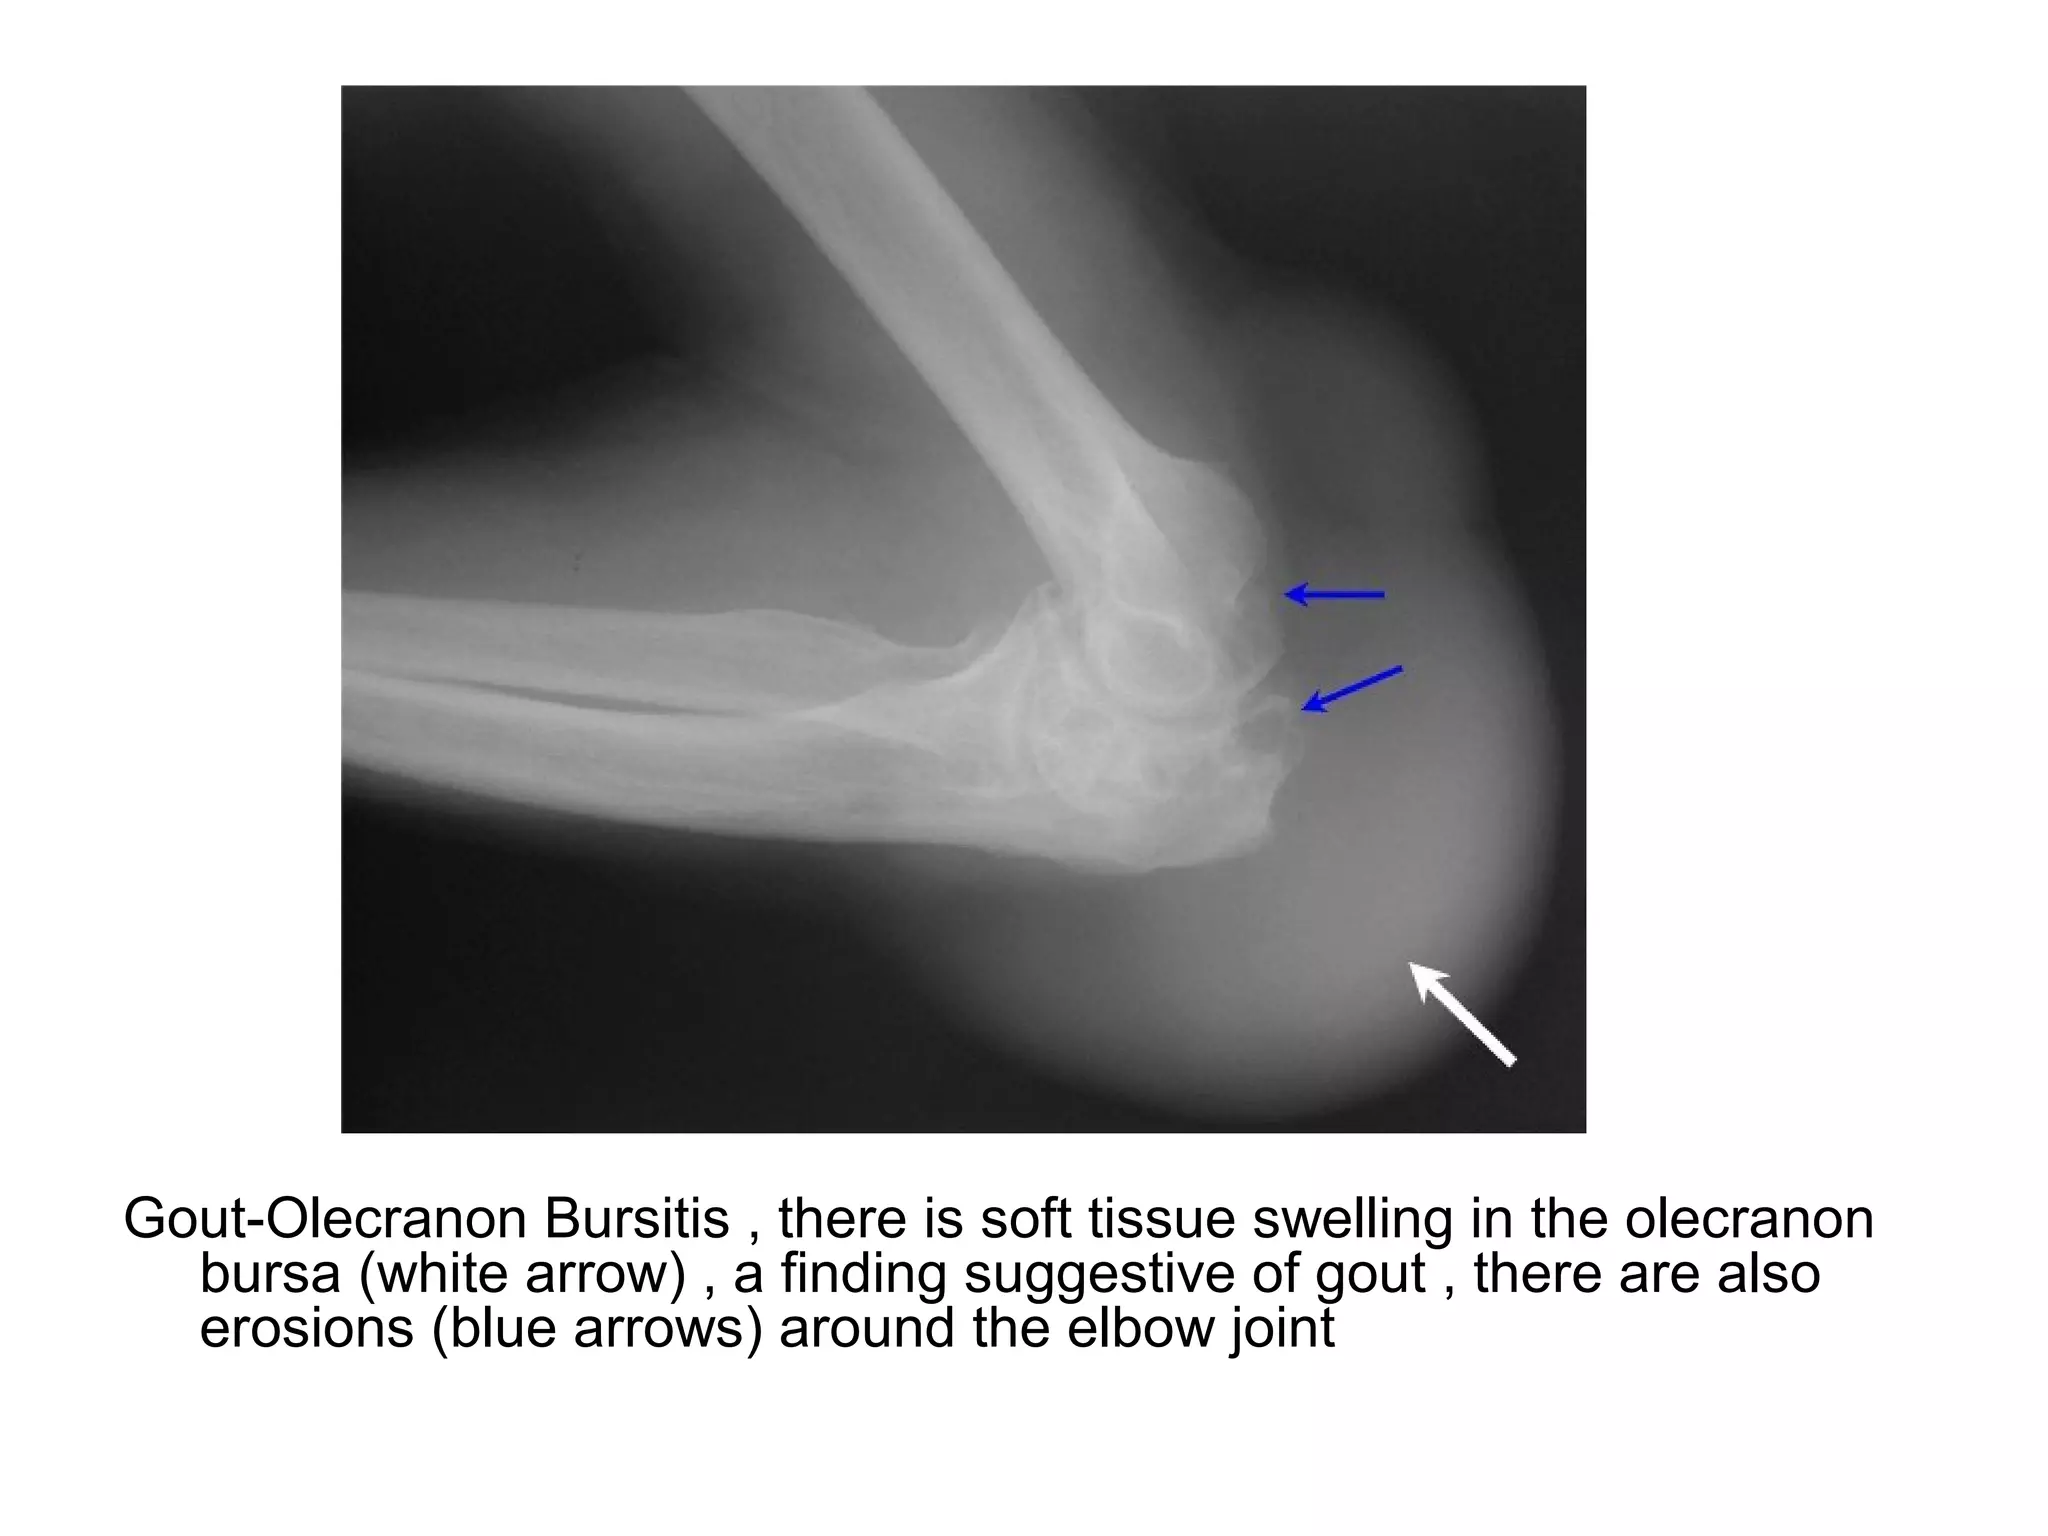

Olecranon bursitis

Gout-Olecranon Bursitis , there is soft tissue swelling in the olecranon

bursa (white arrow) , a finding suggestive of gout , there are also

erosions (blue arrows) around the elbow joint